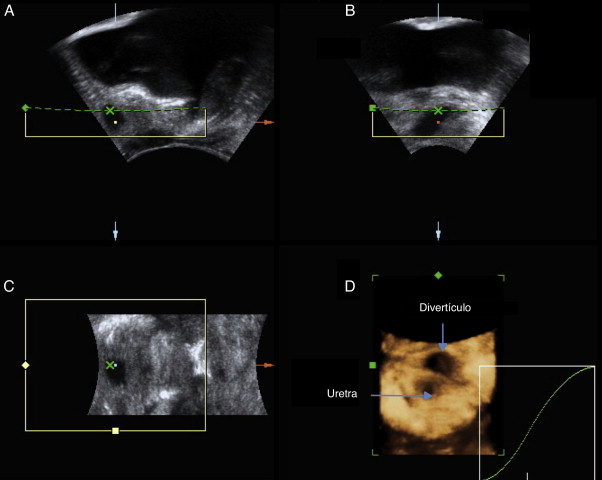

A ecografia permite, em tempo real e com avaliação multiplanar35 , analisar a anatomia uretral e periuretral35 , oferecendo grande detalhe na caracterização dos DUF sem exposição à radiação (ver fig. 2 )35  ;  45 . A visualização do colo diverticular nem sempre é possível35  ;  45 , dificultando o diagnóstico diferencial. Apesar de ser um exame operador‐dependente35 e menos sensível quando existe colapso diverticular35 ou patologia do pavimento pélvico46 , a ecografia apresenta capacidade diagnóstica superior à da uretrocistografia miccional34  ;  35 . Comparativamente à ressonância magnética, poderá ser superior no que concerne à diferenciação entre múltiplos e um DUF único septado41 .

Imagens ecográficas obtidas com sonda transvaginal e reconstrução tridimensional ...

Figura 2.

Imagens ecográficas obtidas com sonda transvaginal e reconstrução tridimensional de divertículo da uretra feminina.

Existem várias vias de abordagem para a captação de imagens ecográficas: as transabdominal e transperineal estão associadas a menor sensibilidade46 . A abordagem endoluminal (transvaginal35 , transretal47 ou transuretral35 ), apesar de ter maior poder diagnóstico, é mais desconfortável para a doente48 . Atualmente, a sonda transvaginal é a mais utilizada39 já que evidencia claramente as relações espaciais entre os DUF e estruturas circundantes49 . Em contexto intraoperatório, a utilização de sondas endoluminais auxilia a dissecção completa das lesões com manutenção da integridade da uretra e colo vesical50  ;  51 .

A técnica de colour‐Doppler permite analisar a vascularização septal e o conteúdo diverticular, sendo particularmente útil na avaliação de massas suspeitas 39 . O preenchimento retrógrado da uretra com contraste sonográfico auxilia a visualização dos orifícios diverticulares e no diagnóstico diferencial com outras lesões periuretrais45 .